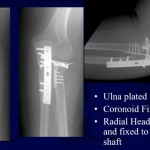

Terrible Triad of Elbow

Terrible Triad of the Elbow Joint